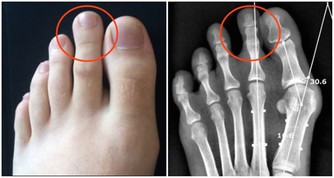

其實,骨質疏鬆和平時所用藥物也有關係,藥物長期使用之下可能造成骨質漸漸流失。

以下藥品有可能造成骨質流失,

因此若平時有長期使用以下藥品且確診為骨質疏鬆症患者,

建議與醫師聯繫,視情況調整用藥,才能做個有「骨氣」的人。